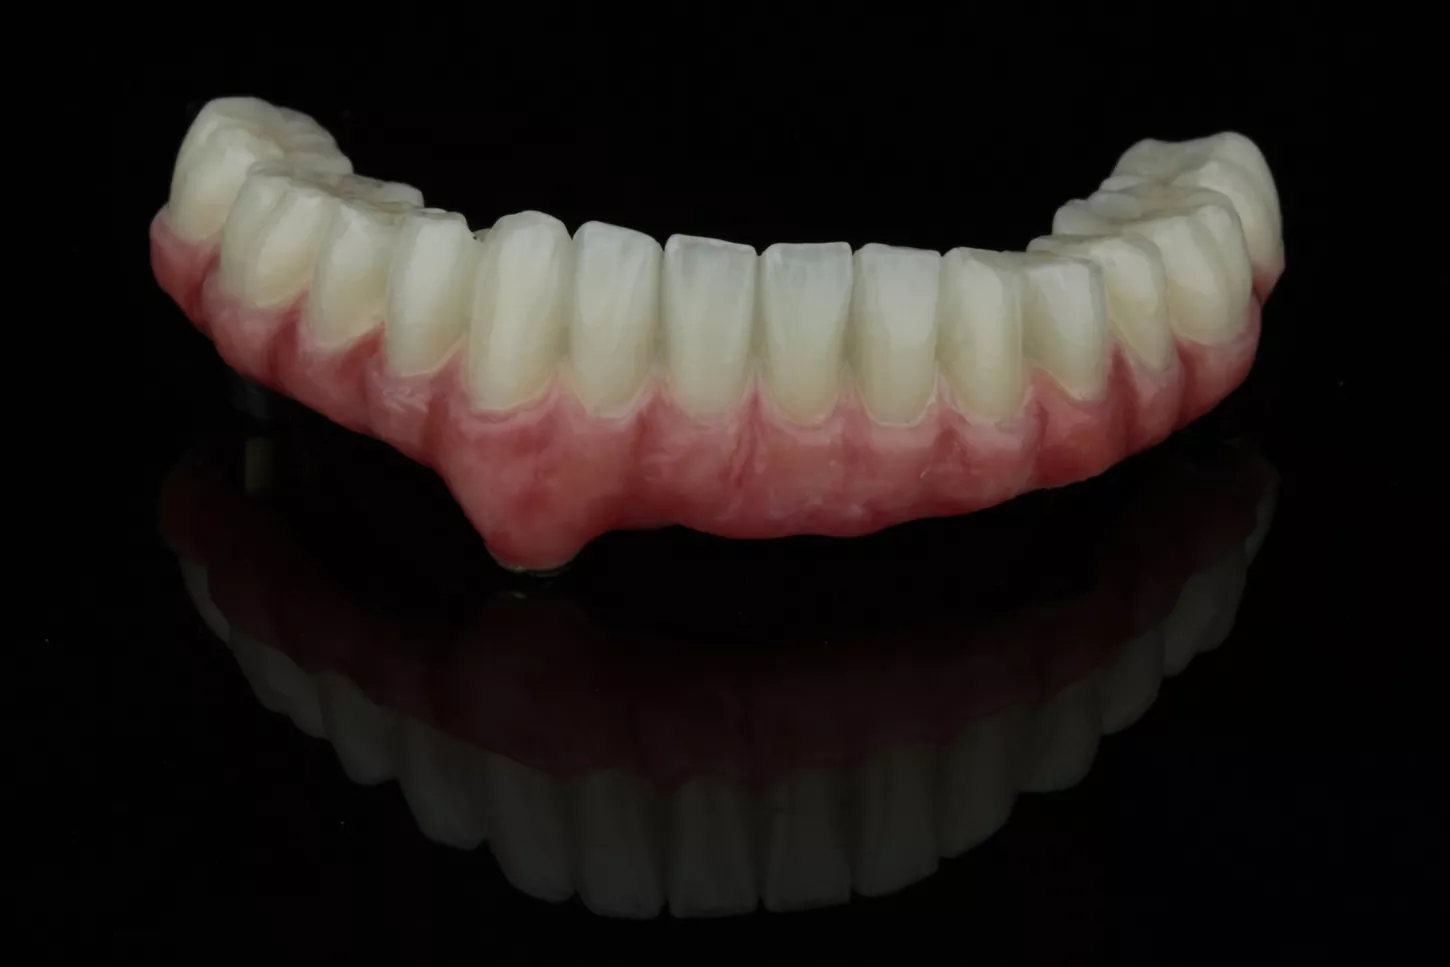

19a. 19b. Images of the lower restoration.

19a

19b